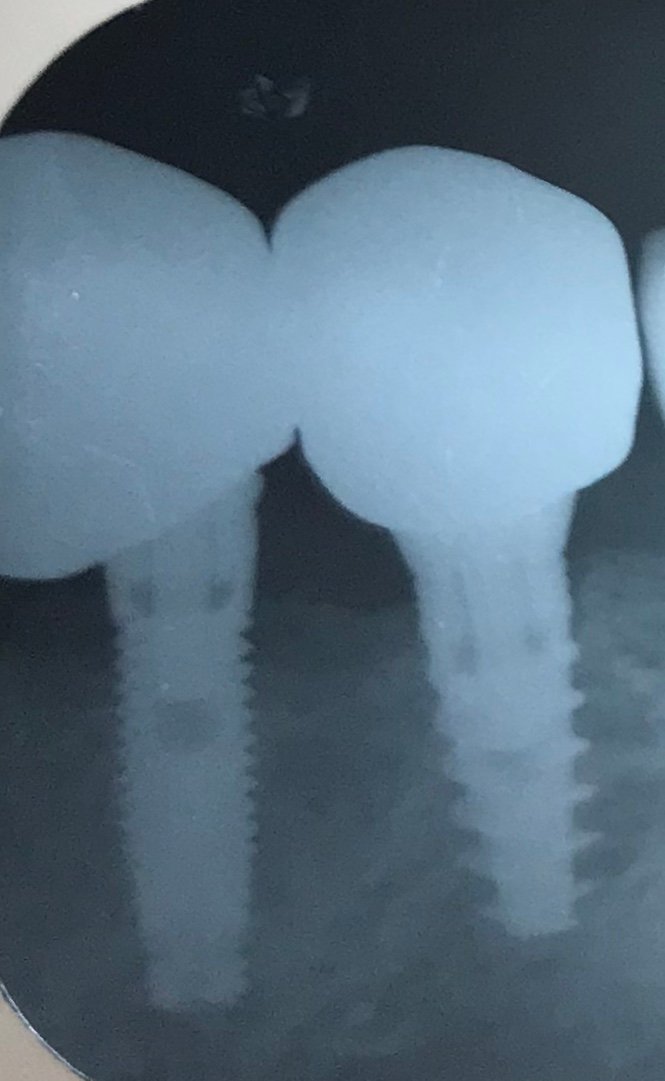

Pcte adulto mayor atendido en EE.UU. me gustaría saber la marca de ambos implantes gracias